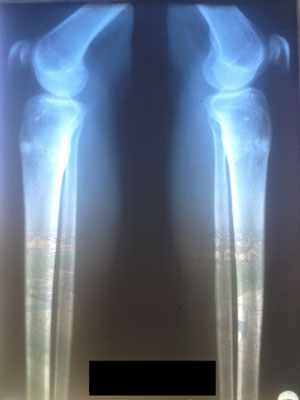

Рентген в 90 дней.

Здравствуйте,Rozali! Приезжайте на снятие аппаратов. Всё отлично! Пересрослось!!!Здравствуйте. Высылаю снимки. Как сращение? Могу приезжать на снятие?